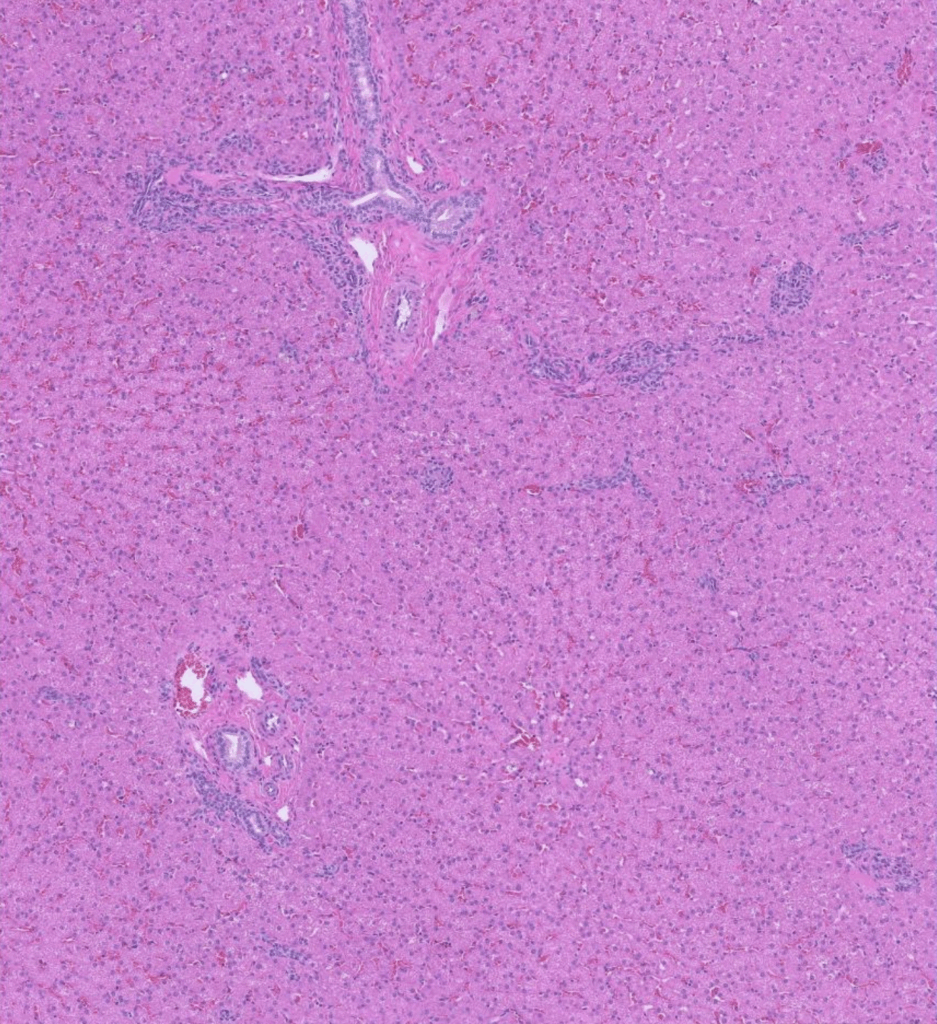

Excisional Liver Biopsy

Liver Biopsy:

Liver: Lobular hypoplasia, diffuse, chronic, moderate, with hepatocellular atrophy, arteriolar reduplication, and mild biliary hyperplasia. The vascular changes in this liver represent a stereotypic response to insufficient portal blood supply resulting from either a congenital shunt, portal vein hypoplasia (microvascular dysplasia), or acquired portal hypertension due to cirrhosis or extrahepatic causes.